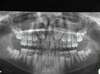

Panoramique